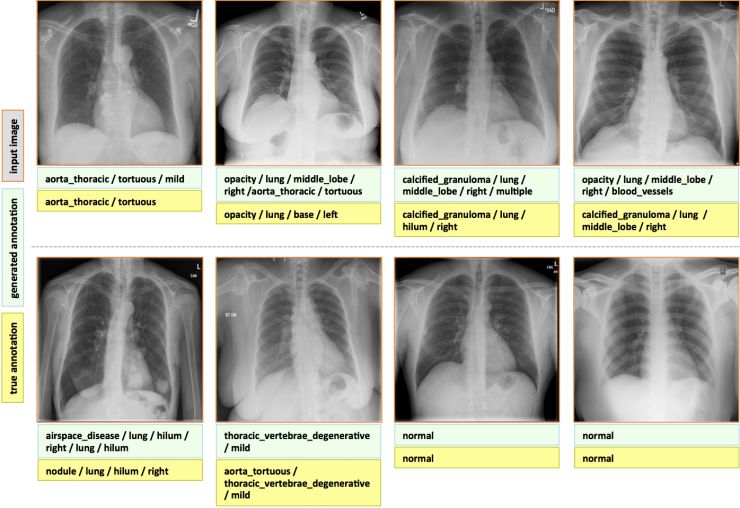

• 医健资讯|健康保卫战:深度学习在使用胸部X光照片预测疾病上的应用 9年前

贝塞斯达(美国马里兰州中部城市)国立卫生研究院的研究者们开发出了一套基于深度学习的用来从胸腔X光照片中检测疾病的算法框架...